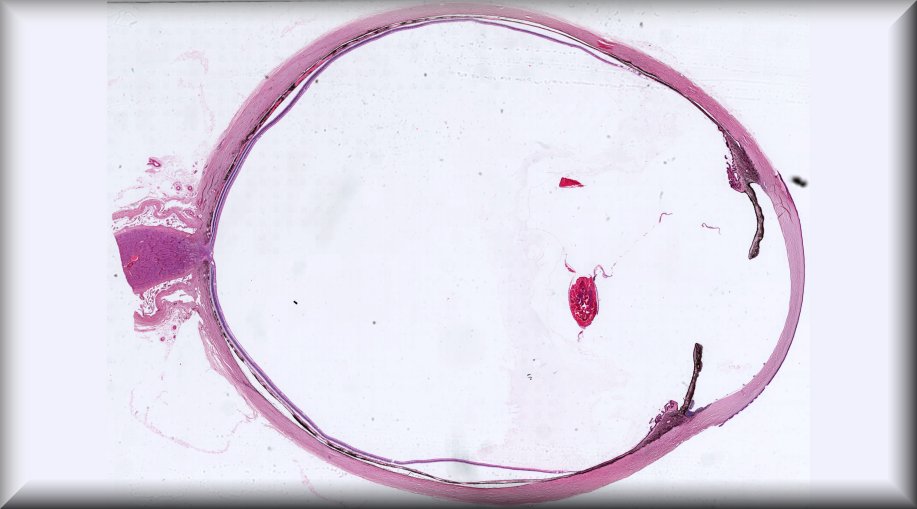

María Antonia Saornil (Valladolid): 19-year-old male patient who, in the last 3 months, had a progressive and extensive protrusion in the temporal sclera of the left eye. The patient also reports noticing loss of nasal visual field. |